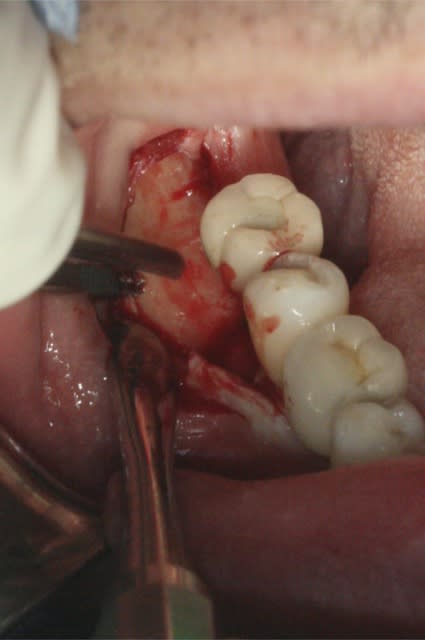

image1: incision verticale + décollement du lambeau de proche en proche

Désolé pour la qualité, c'est tout ce que j'ai..

Ram1 cdupuy - Eugenol

Ram3 dxbjkr - Eugenol

Ram4 ozorff - Eugenol

Ram2 bdyujf - Eugenol

Ram5 jvmsow - Eugenol

Ram6 wpzb9d - Eugenol

Ram7 zuiuy2 - Eugenol